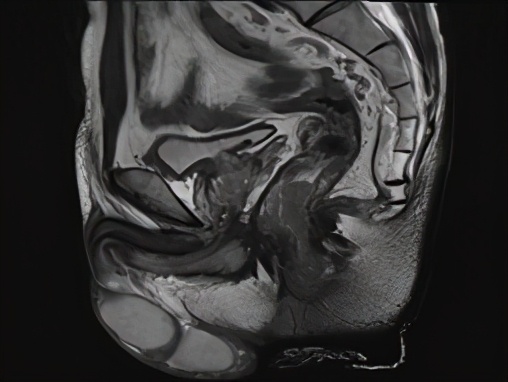

男,58岁,距肛1cm直肠腺癌,3b期,MRF+,复发风险极高危组,有强烈保肛愿望;接受同期放化疗,放疗结束6周后评价为临床完全缓解,接受观察等待疗法。观察至今(2020.11)无复发,肛门功能完全正常,生存质量良好。

图1b 治疗前MRI(2016.8)